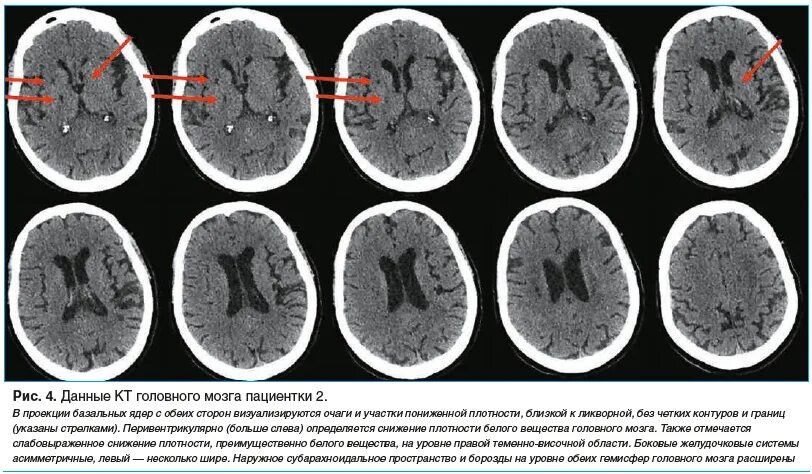

Данные кт